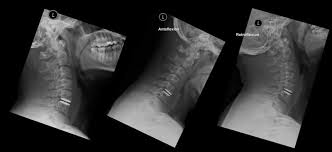

Rezidiv Bandscheibenvorfall Nach Op Dr Christopoulos